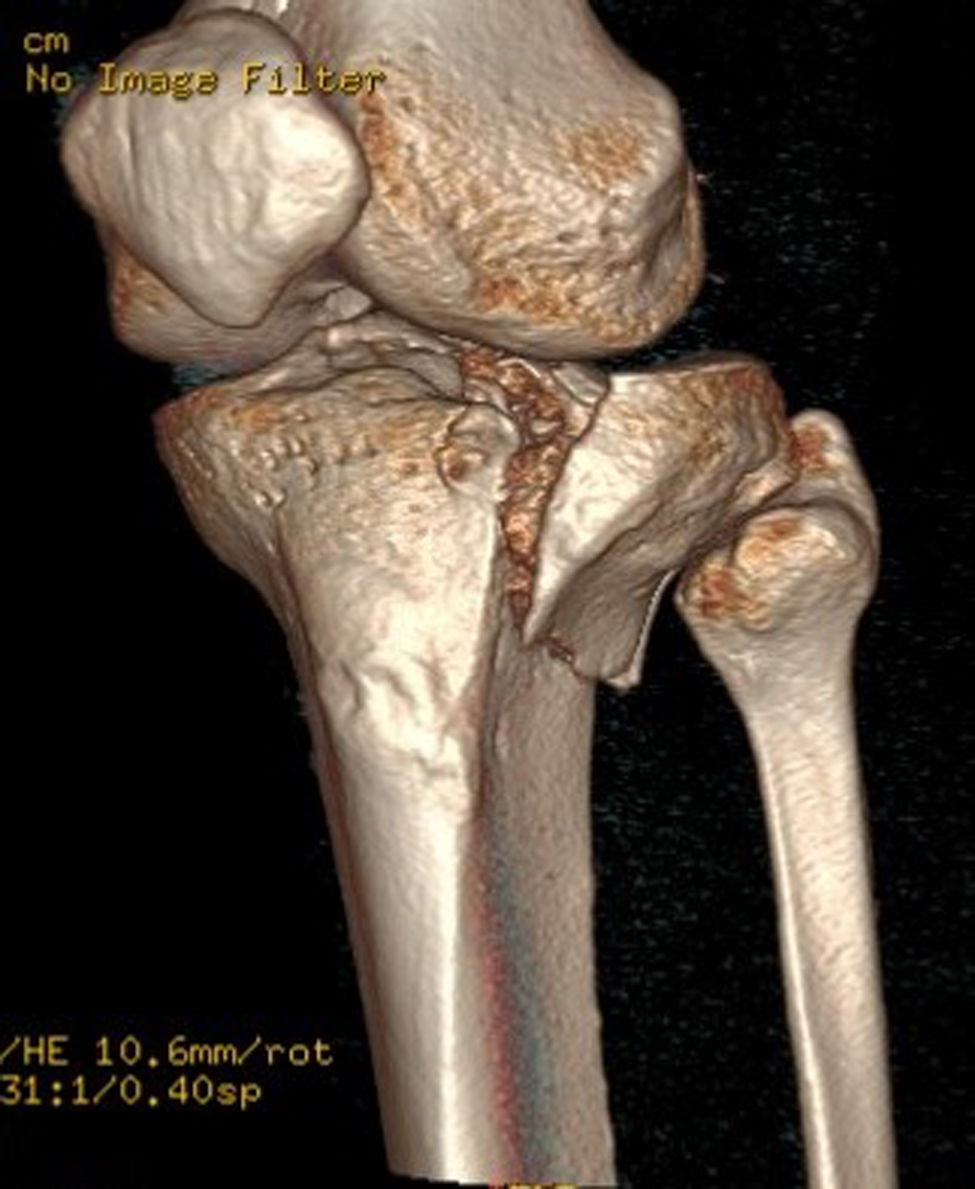

Existen varias clasificaciones de las fracturas de la meseta tibial basadas en su localización y en su desplazamiento. La más utilizada es la de Schatzker, que divide las fracturas en 6tipos, de menor a mayor gravedad. La clasificación AO es la más integral y extensiva que correspondería con las 41 A-B-C. La clasificación de Luo de las tres columnas es la más simple con vistas a una posible planificación quirúrgica. En todos los estudios epidemiológicos las fracturas más frecuentes son las Schatzker tipo2 o las 41B3 de la AO que corresponden al patrón de fractura unicondilar externo debido a mecanismo en valgo con depresión y línea de fractura vertical1-7. La aparición de la TC y de los modelos 3D ha contribuido enormemente a la descripción de los diferentes patrones de fractura con vistas a una adecuada planificación quirúrgica1-6, describiéndose el área posterolateral como la de mayor incidencia en líneas de fractura y mala reducción2,6 (fig. 1).

En el estudio de TC se hizo una adquisición volumétrica en un equipo multicorte a 0,6mm con posteriores reconstrucciones multiplanares de 1,5mm de espesor y 1,0mm de intervalo. En la reconstrucción en el plano coronal se analizó el punto de mayor depresión de la fractura en mm que se corresponde con el escalón articular máximo y la anchura máxima/diámetro transversal en mm; en el plano sagital se midió el diámetro máximo anteroposterior en mm del escalón articular y la caída máxima (slope) de la meseta tibial externa en grados (fig. 3). En el post-procesado en el plano axial se delimitó el contorno de la fractura y se calculó el área afecta en cm2, así como el diámetro mayor anteroposterior y la anchura máxima en mm (diámetros máximos anteroposterior y transversal) (fig. 4).